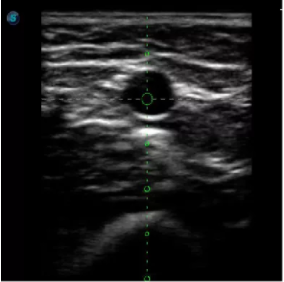

2宮腔專(zhuān)用探頭

多數(shù)的生殖科醫(yī)生對(duì)于受精卵的植入采用憑經(jīng)驗(yàn)操作或是使用傳統(tǒng)腔內(nèi)探頭引導(dǎo),同樣存在手術(shù)空間小、受精卵放置位置不確定等風(fēng)險(xiǎn)。專(zhuān)業(yè)的宮腔專(zhuān)用探頭,配合專(zhuān)用的窺器使用,為醫(yī)生提供最大的手術(shù)視野。

胎移植臨床圖